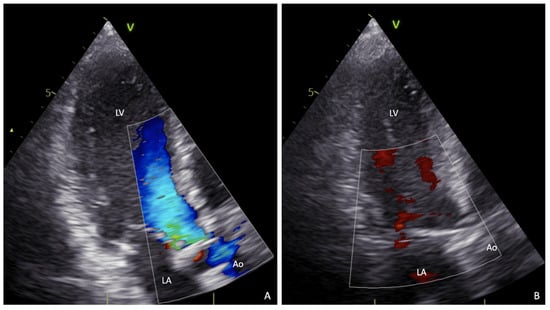

During the ICU post-operative stay, the patient required circulatory high-dose inotropic (≥0.1 mcg/kg/min of epinephrine and norepinephrine) and mechanical support with IABP due to severe biventricular dysfunction. One cycle of levosimendan 0.4 mcg/kg/min was successfully performed over 96 hrs. After six days, the respiratory function progressively recovered, and the patient was extubated. Further application of CPAP guaranteed optimal oxygen saturations. Development of post-operative fever and evidence of Candida parapsilosis on the tip of the central venous catheter and blood cultures as well, required the introduction of 100 mg/day anidulafungin first, followed by antibiogram-guided 400 mg per day of fluconazole, with a subsequent decrease of inflammation parameters. After three weeks, the SARS-CoV-2 test finally resulted negative as well as blood cultures and a thoracic CT scan showed an almost complete resolution of COVID-19 pneumonia (Figure 2B and Supplemental Video S2). The pre-discharge transthoracic echocardiography (TTE) showed a good post-operative result of the aortic bioprosthesis (mean transvalvular gradient 12 mmHg), no paravalvular leaks, and a residual mild MR without increased gradient (Figure 3 and Supplemental Video S3).

Figure 3.

Post-operative transthoracic echocardiography (TTE). Long-axis three-chambers view in late diastole (A) and systole (B) at color doppler TTE showing no paravalvular leak (PVL) of the AVR and good result of the mitral valve repair.